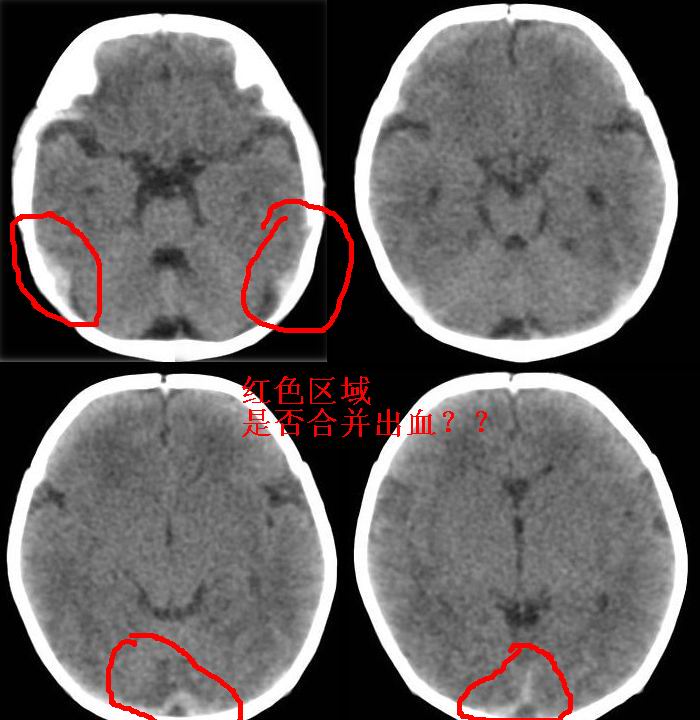

新生儿3天,超过预产期5天剖宫产,有缺氧病史,具体评分不详,现反应差,肌张力低,前囟平,原始反射存在,无苦闹等。

kaolv小脑幕,后纵裂区蛛网膜下腔出血;轻度脑肿胀

矢状窦旁征——支持蛛网膜下腔出血

sah。